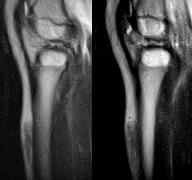

标题: PED0931:男,5岁,发现双小腿软组织肿块1年,质地中等,无 [打印本页]

标题: PED0931:男,5岁,发现双小腿软组织肿块1年,质地中等,无